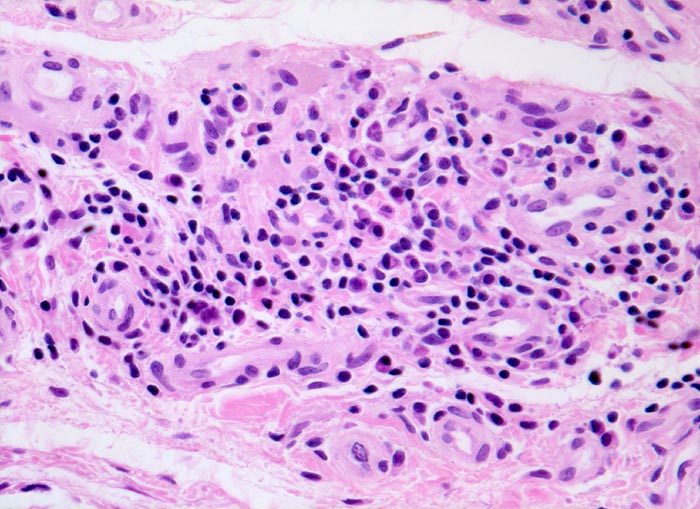

Synovialitis bei chronischer Polyarthritis

Lymphoplasmazelluläres Entzündungsinfiltrat im Stroma. Die Plasmazellen sind gut erkennbar an der perinukleären Zytoplasmaaufhellung.

Bekannte seropositive chronische Polyarthritis.

Der Nachweis von Plasmazellen ist typisch, aber nicht beweisend für eine chronische Polyarthritis.

Histologie

200